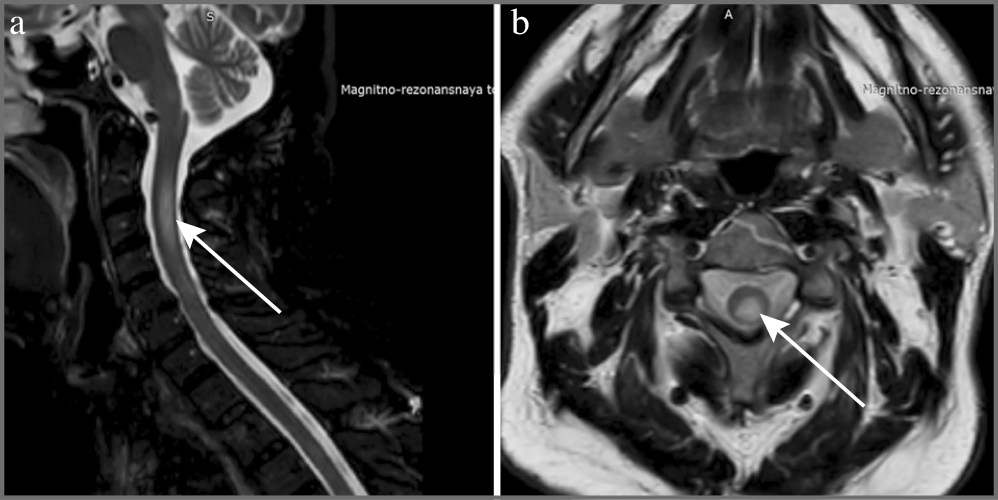

КТ органов грудной клетки от 07.05.2020: вирусная пневмония КТ-4. МРТ шейного и грудного отделов позвоночника с внутривенным контрастированием от 08.05.2020: МР-картина поражения спинного мозга на шейном (СII–СIII) и грудном (ThIII–ThV) уровнях в виде очагов демиелинизирующего характера (рис. 3).

Рис. 3. МРТ шейного отдела спинного мозга в Т2-взвешенном изображении пациента Г. от 08.05.2021. Очаговые изменения МР-сигнала в СII–СIII сегментах: а – сагиттальный срез; b – аксиальный срез.